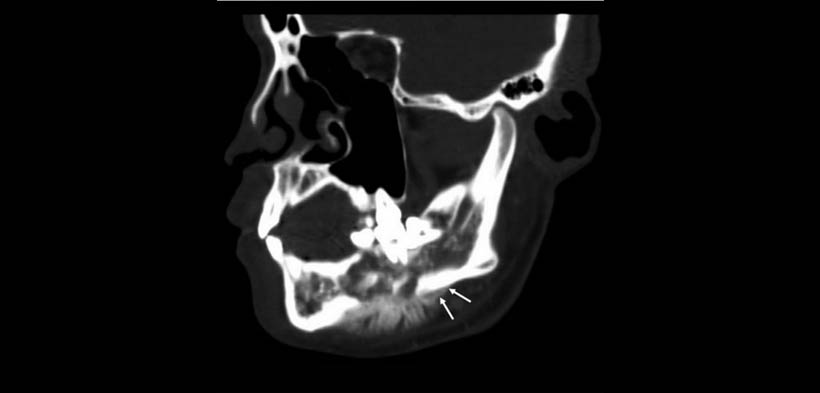

Fig. 3 Osteosarcoma a nivel del cuerpo mandibular en un hombre de 18 años de edad. TAC, la reconstrucción multiplanar en la vista sagital, muestra mostrar una reacción perióstica clásica en “rayos de sol” (flechas blancas)